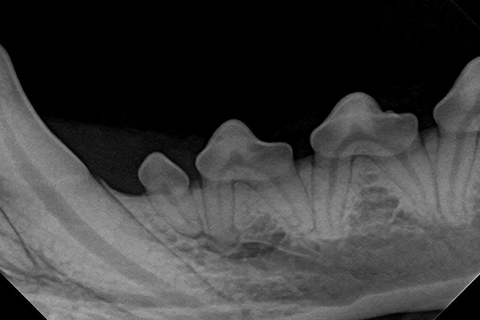

Dental Care

Regular dental cleanings are important in maintaining your pet’s teeth as well as their overall health.